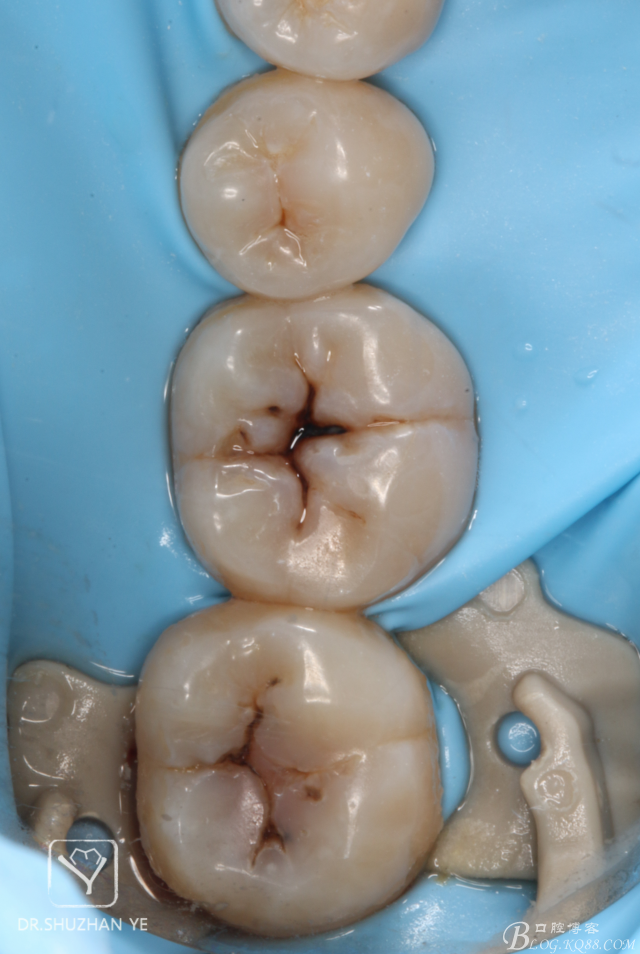

3、上橡皮障

4、去齲后涂布齲顯示劑,保證去齲充分

5、去齲完成